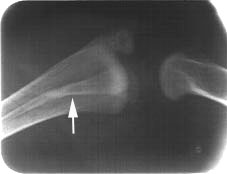

Tomada radiográfica lateral evidenciando a superposição da fíbula com o tíbiotarso (seta), alvo de nossa exploração cirúrgica.